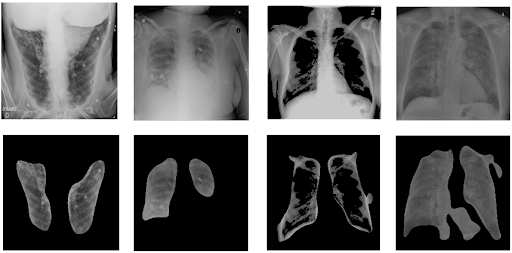

Augmented Training Data